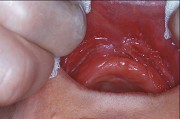

1.组图是牙龈瘤患者,有关此病的描述不正确的是 ( )![]() ![]() ![]() ![]() |